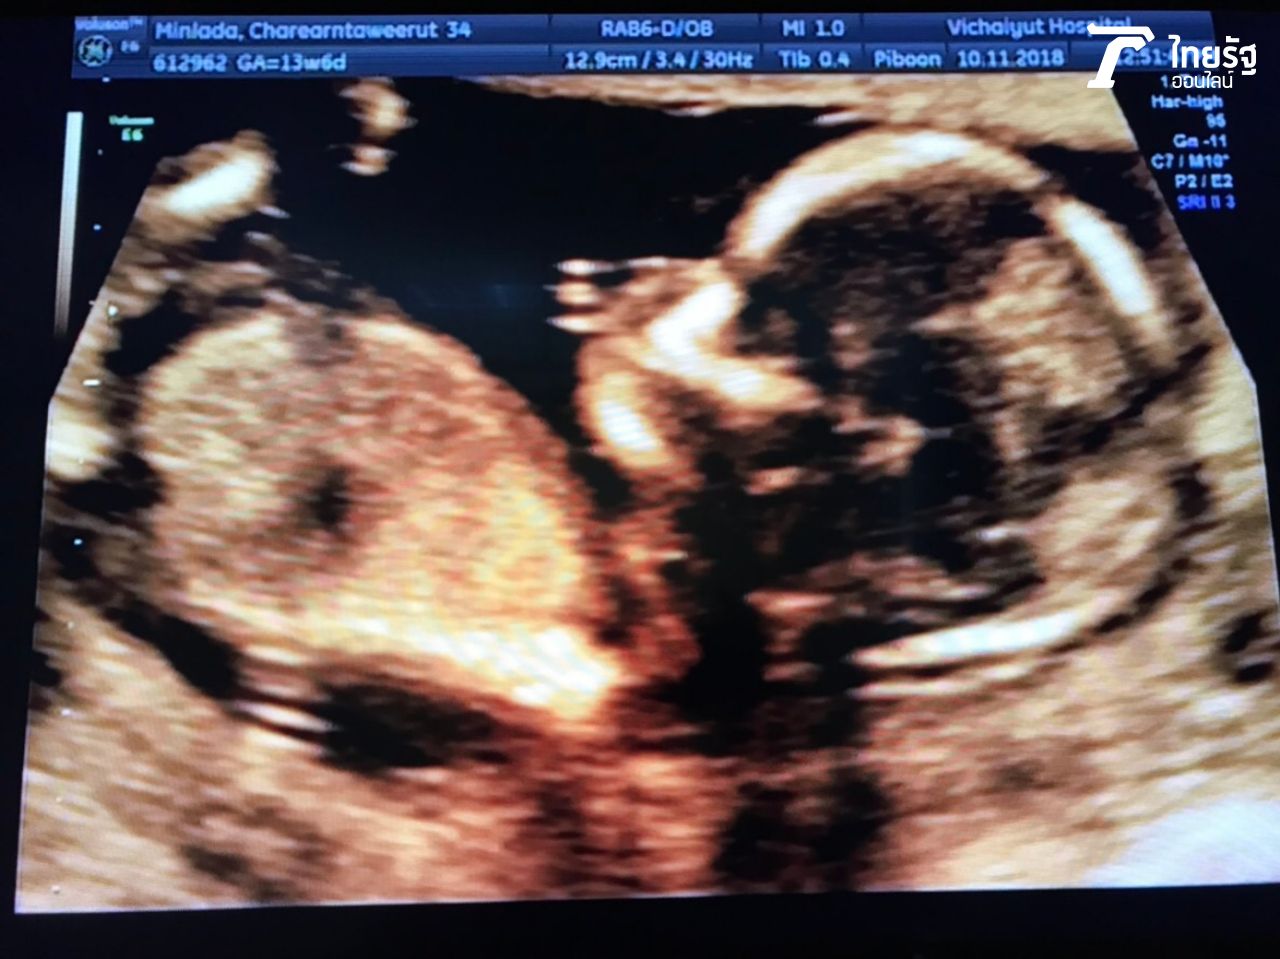

อุ๊ มิณทร์ลดา เปิดใจด้วยน้ำเสียงสดใสกับบันเทิงไทยรัฐออนไลน์ "ตอนนี้หนูตั้งท้องเกือบ 4 เดือนค่ะ สุขภาพแข็งแรงทั้งแม่ลูก หมอให้วิตามินมาบำรุงลูกด้วยค่ะ ก็ได้ลูกชายสมใจสามี กะว่าจะมีลูกอีกคน เพราะอยากได้ผู้หญิงด้วยค่ะ กำหนดคลอดกลางปีหน้า อยากเว้นช่วงนิดหนึ่ง แล้วกะท้องคนต่อไปเลยค่ะ".